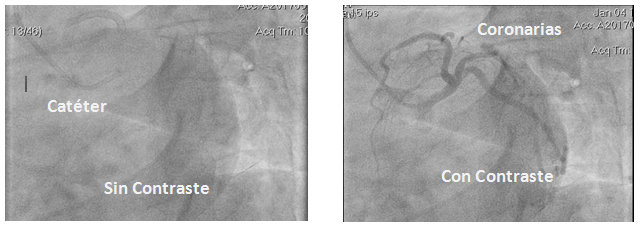

Llegado a destino el extremo del catéter, desde el extremo opuesto (que queda fuera del organismo) se inyecta entonces el líquido de contraste con una jeringa especial a rosca. Cuando el contraste llega a la cavidad, esta se opacifica y se obtienen filmaciones desde distintos ángulos para observar los vasos desde distintos puntos de vista.

Imagen 2